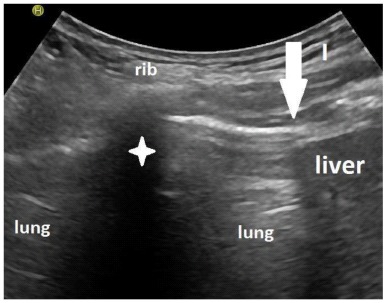

Methods: 84 patients were included when they were able to breathe at least 10 minutes over a t-piece and sit upright for at least 5 minutes. The diaphragmatic function was estimated sonographically using the up and downward movement of the lung silhouette. Sonographic follow-ups were performed for over 18 months. The survival rate, outcome and changes in diaphragm mobility were investigated.